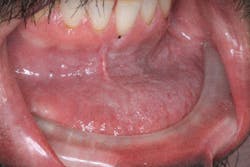

Pathology ... it’s always going to be part of the clinical assessment with our patients. And if they smoke or chew tobacco, we need toBreakthrough Clinical oral pathology case: No. 22